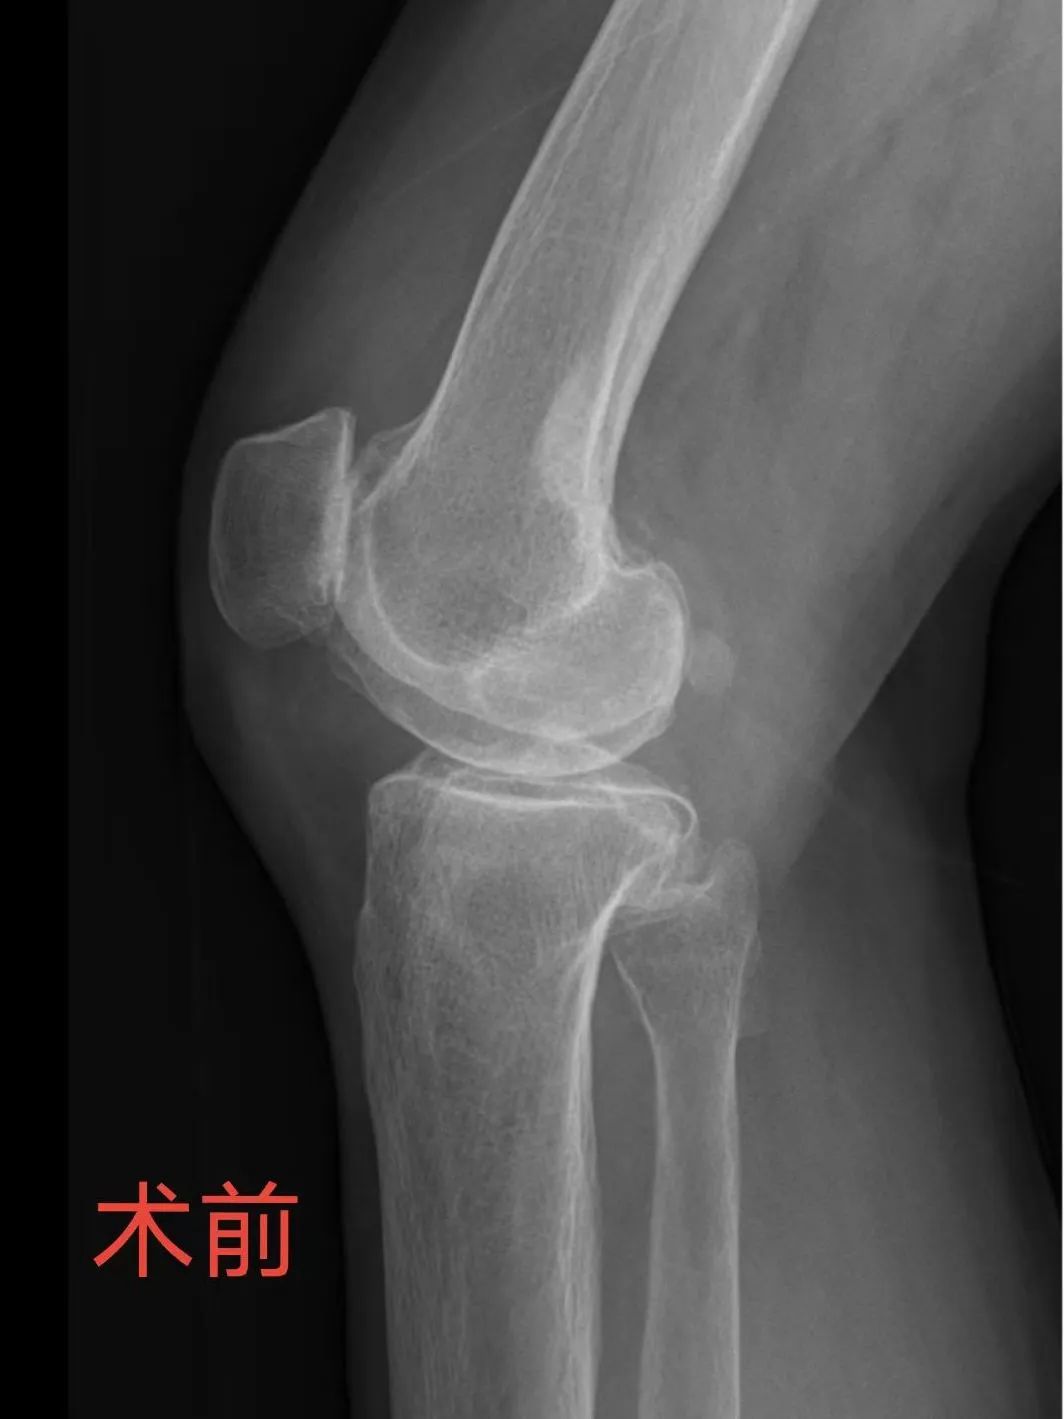

俗話說“傷筋動骨一百天”,但已75周歲的王阿婆在我院做完膝關(guān)節(jié)置換術(shù)后自己走出手術(shù)室。家住南安的王阿婆膝痛十余年,因?qū)κ中g(shù)有恐懼和抵觸,故未進行規(guī)范治療。最近,她疼痛得難以忍受,且嚴重影響日常生活和行走,沒辦法,只能來醫(yī)院求助。我院骨科蘇新瑩主治醫(yī)師接診。蘇醫(yī)師經(jīng)過詳細體查及查閱X光片后,診斷為膝關(guān)節(jié)骨性關(guān)節(jié)炎(也就是常說的老寒腿)。目前,僅靠單純的吃藥、打針等保守治療基本無效,建議行膝關(guān)節(jié)置換術(shù)。骨科黃進福主任醫(yī)師和呂培閩副主任醫(yī)師對患者病情進行全面評估,制定了治療方案和手術(shù)計劃。經(jīng)過深入溝通后,王阿婆及其家屬同意手術(shù)治療。

▲左側(cè)為術(shù)前X片,右側(cè)為術(shù)后X片